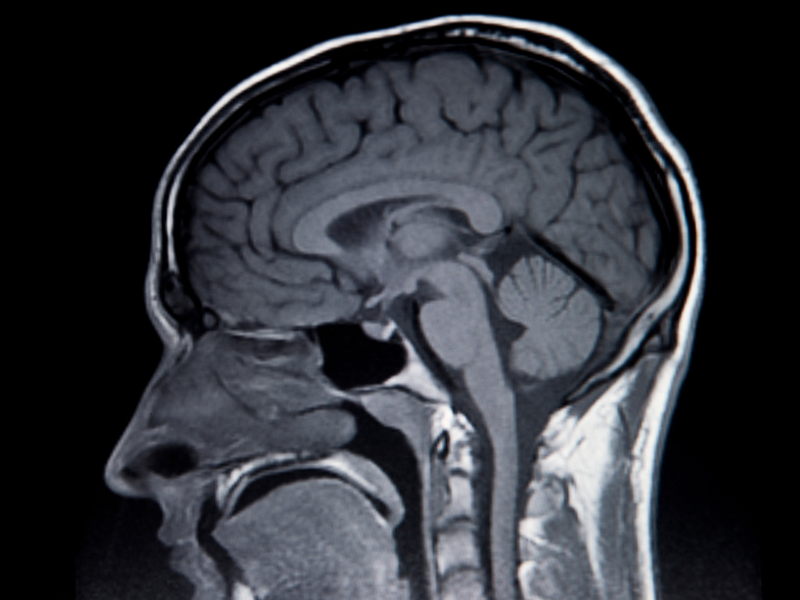

Cinco años después del inicio de sus síntomas, el participante se sometió a una cirugía para insertarle 256 electrodos de silicio, cada uno de 1,5 mm de longitud, en una región del cerebro que controla el movimiento. Maitreyee Wairagkar, neurocientífica de la Universidad de California en Davis y coautora del estudio, y sus colegas entrenaron algoritmos de aprendizaje profundo para capturar las señales cerebrales del hombre cada 10 milisegundos.